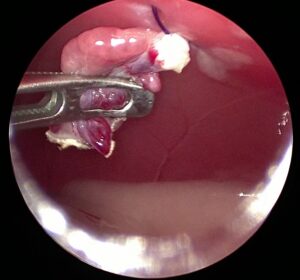

腹腔内で完全に分離させた卵巣を摘出しているところ